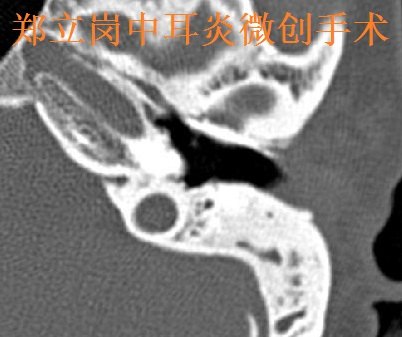

郑立岗中耳乳突炎耳内镜微创手术第584江西赣

364x442 - 22KB - JPEG